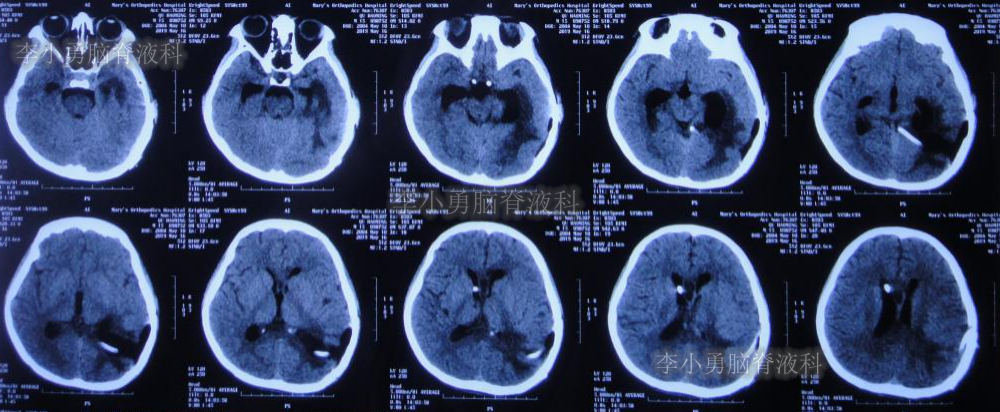

2019年3月26日患者突发头痛及呕吐,随后出现晕厥。急救车送至河南省周口市某医院。行头颅CT(图-1):脑室内出血,次日急诊给予行双侧脑室外引流术(图-2)(第一次的脑室外引流术)。

图-1:2019年3月26日头颅CT:脑室内出血

图-2:2019年3月27日头颅CT:双侧脑室外引流术后